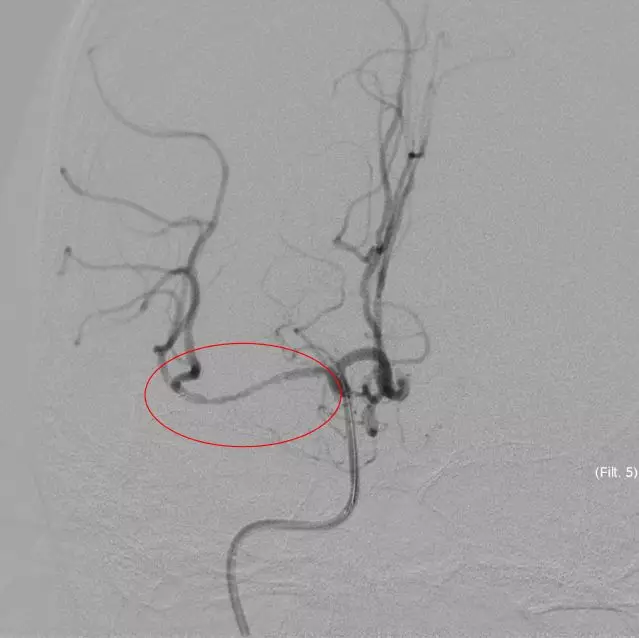

立即DSA(08-03日 13:24分)

5MIN后